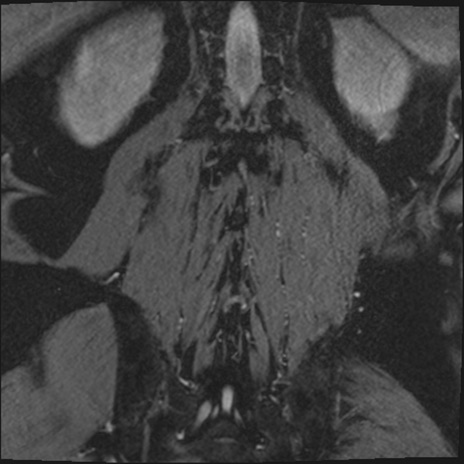

【整形】TIPS症例2 腰椎MRI 3D(冠状断像)

【症例】70歳代男性

【主訴】左下肢痛

【現病歴】2週間前くらいから腰痛、左下肢痛あり。左臀部から大腿、下腿外側のしびれが常時ある。歩行とともに同部位の痛みあり。

【身体所見】Lasegue70-/60+、Bragard-/±、PTR ±/±、ATR -/-、IP 5/5、TA 5/4、TS 5/5、EHL 右第1足趾なし/3、FHL 5/5、hypersthesia(-)、足背動脈触知良好

異常所見と診断は?